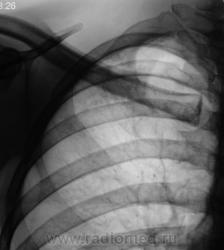

Пациент, как чаще бывает, взят на контроль дообследован и отправлен к фтизиатру с диагнозом (предварительным) - очаговый туберкулёз.

Томографируем.

Конечно, берем на "контроль".

Зову коллегу фтизиатра. Коллега, весьма эмоционально вспоминает "свою маму", да и "маму пациента", что варнякает об инфильтративном, и о том, как такое могло статься, посылает пациента в областную контору, где все утверждается, пациент стационарно получает лечение.

Прошло достаточное количество времени, и сегодня пациент пришел на плановое рентгенологическое исследование. Снимки ниже.